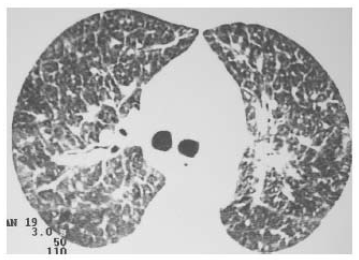

Uma paciente de 49 anos de idade, sem antecedentes patológicos conhecidos, com tabagismo importante (80 anos-maço) e com importante perda de peso nos últimos meses, compareceu a uma consulta ambulatorial apresentando dispneia progressiva associada a dessaturação em ar ambiente. Negou febre ou outros sintomas. No exame físico, constatou-se que a paciente apresentava saturação de 85% a.a., sem sinais de desconforto respiratório e com importante baqueteamento digital. Foi encaminhada ao setor de imagem, onde realizou tomografia computadorizada de tórax com um dos cortes representados na figura a seguir.

A paciente apresentava baciloscopia negativa e CEA acima do percentil 99 do teste.